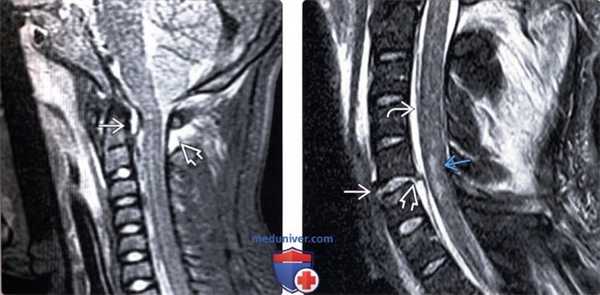

(Слева) На сагиттальном T2*GRE МР-И гиперфлексионного повреждения шейного отдела позвоночника с двусторонним вывихом позвонка отмечается разрыв ЗПС и перелом переднего края тела С7. В толще спинного мозга на уровне С5-С7 определяется очаг контузии и гематома.

(Справа) На фронтальном Т2-ВИ ребенка с переломом правого мыщелка затылочной кости (не показан) отмечается частичный отрыв правой крыловидной связки от мыщелка затылочной кости.